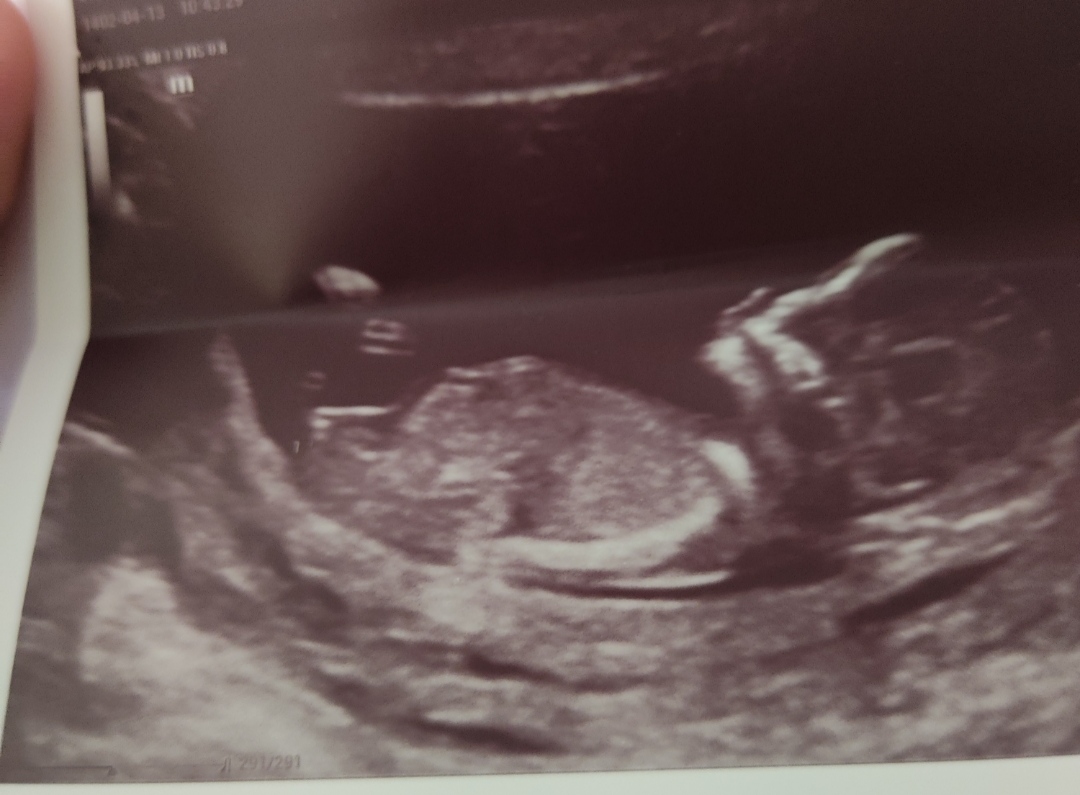

سونو ان تی میرم و بخاطر پهلو درد شدید سونو کلیه ام انجام میدم تو رو خدا برام دعا کنید بچم مشکلی نداشته باشه و سالم باشه و خودمم مشکلی نداشته باشم با خوشحالی برگردم انشالا هر چی از امام هادی میخاین تو این روز از خدا براتون عیدی بگیره الهی آمین